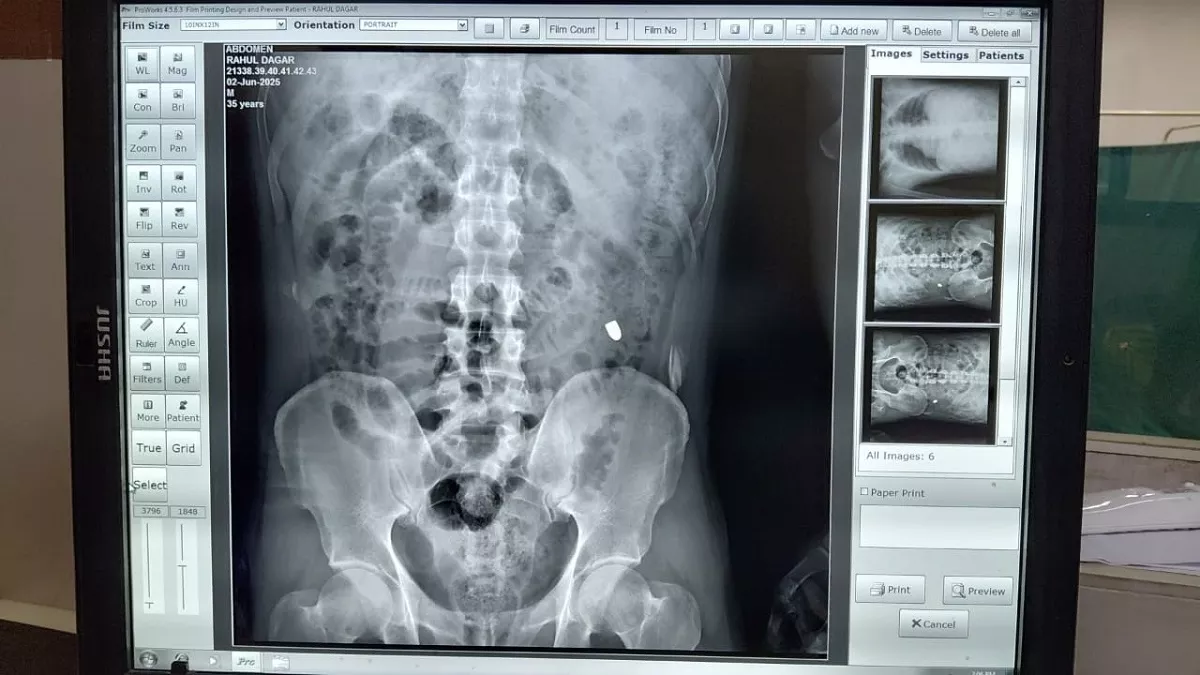

राहुल डागर हत्याकांड: एक्स-रे कराने पर पेट में फंसी मिली एक गोली, पोस्टमार्टम रिपोर्ट में हुए चौंकाने वाले खुलासे

गाजियाबाद के राजनगर एक्सटेंशन में राहुल डागर की हत्या के बाद पोस्टमार्टम रिपोर्ट में खुलासा हुआ कि उन्हें दो गोलियां मारी गई थीं। एक गोली गर्दन को छूकर निकल गई जबकि दूसरी चेस्ट में लगी और पेट में फंस गई जिससे आंत में संक्रमण फैल गया। पुलिस ने दोनों गोलियां जांच के लिए भेज दी हैं।

गोली को लेकर चर्चा हुई और तय किया गया कि शव का एक्स-रे कराया जाना जरूरी है। दरअसल हत्यारोपियों ने दो गोली चलाई थी। पोस्टमार्टम के दौरान देखने पर पाया कि एक गोली गर्दन के पास हल्का घाव करते हुए बाहर निकल गई है, जिसका खोखा भी पुलिस ने बरामद कर लिया है।

दूसरी गोली चेस्ट में लगी और पेट में जाकर फंस गई। इसके लगने का घाव तो दिखा, लेकिन निकलने का नहीं मिला। ऐसे में एक्स-रे जरूरी हो गया। पुलिस शव को लेकर जिला एमएमजी अस्पताल में पहुंची। यहां शव का एक्स-रे किया गया। पेट का एक्स-रे करने पर साफ पता चला कि दो गोली लगी थी। एक गोली गर्दन के बाहरी हिस्से में लगी और पार हो गई। इसका खोखा भी पुलिस को मिल गया।

सूत्रों के अनुसार दूसरी गोली चेस्ट के निचले हिस्से में सीधी तरफ लगी और उल्टी तरफ किडनी के पास जाकर फंस गई। विशेषज्ञों के अनुसार इस गोली से आंत खराब हो गई। पूरे पेट में इंफेक्शन फैल गया और युवक की मौत हो गई। इस गोली को भी पुलिस को सौंप दिया गया है। दोनों गोली जांच के लिए भेज दी गईं है।